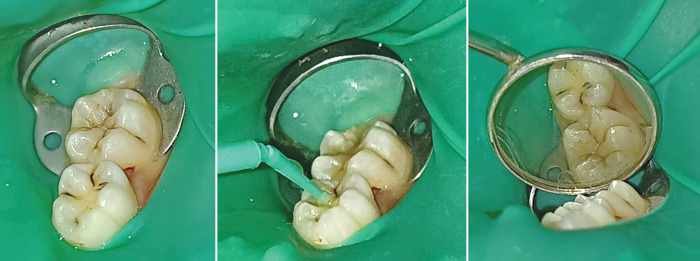

Materials and methods: This study employed a mixed-methods approach, combining quantitative data on clinical outcomes with qualitative patient and provider feedback. The study design included pre- and posttreatment assessments to evaluate the effectiveness of each preventive measure. A total of 300 participants were recruited for the study, divided into three groups based on the preventive treatment received: group A-100 participants received dental sealants, group B-100 participants received SDF treatment, and group C-100 participants received NSF treatment. Participants included children aged 6-12 years and adults considered at high risk for caries due to factors such as socioeconomic status, previous dental history, or special healthcare needs.

Results: In group A, there was a significant 75% reduction in caries incidence over the 12-month period. Follow-up examinations indicated that sealants remained intact in 90% of cases. Group B reported an 85% success rate in caries arrest, with most lesions remaining stable. In group C, 82% of carious lesions were arrested, with patients reporting less staining compared to those treated with SDF. Follow-up showed high retention of the treatment's effectiveness. Among patients treated with sealants, 90% expressed satisfaction with the application process and perceived effectiveness. SDF and NSF acceptance in group B, 88% of patients reported comfort with SDF treatment. In group C, 92% expressed a preference for NSF due to reduced staining concerns, indicating a strong acceptance of these newer treatments.